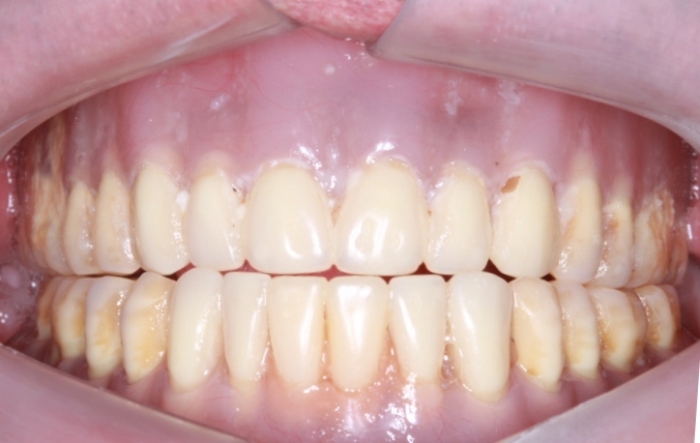

Imagem Inicial,em 2015

Sorriso inicial, em 2015